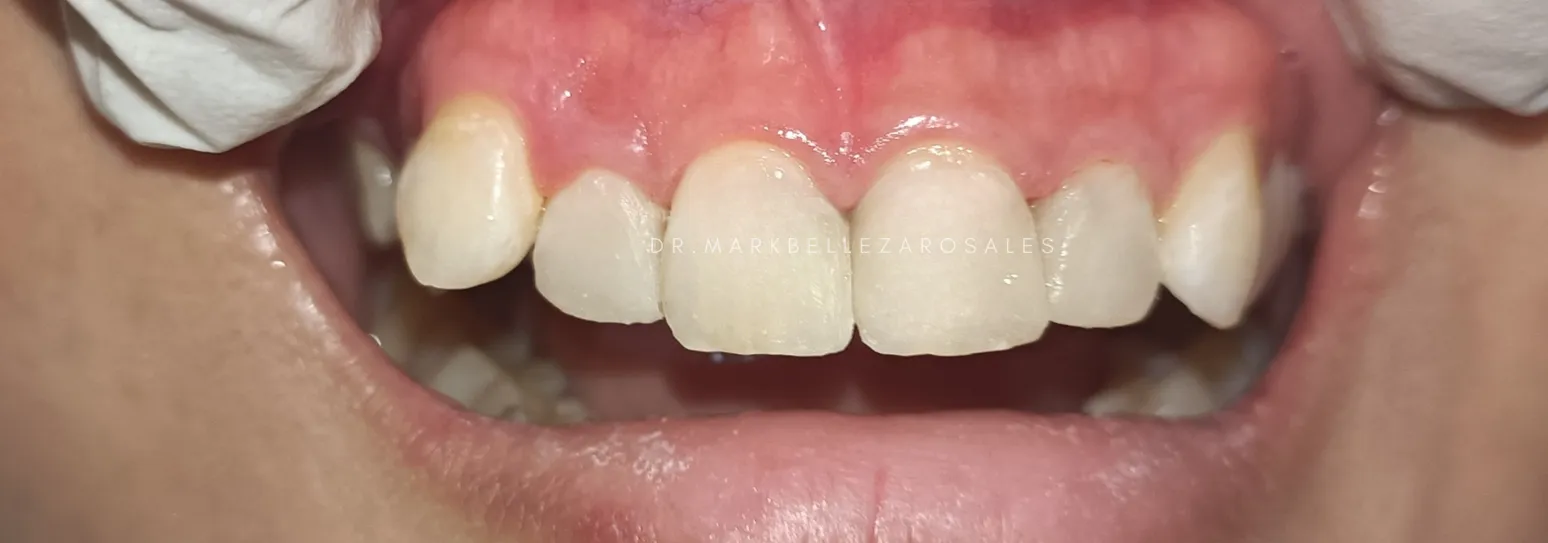

A zirconia crown is a tooth-colored dental cap used to restore a damaged, weakened, or heavily filled tooth. It provides exceptional strength, protects the remaining tooth structure, and offers a natural appearance while allowing you to chew and smile with confidence.